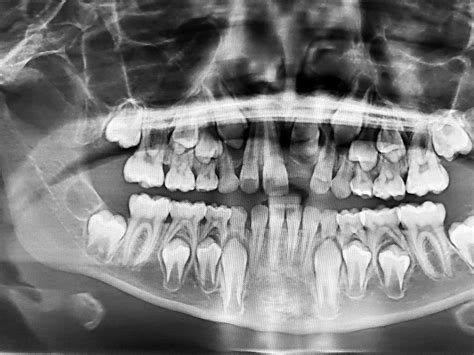

La odontopediatría es una rama de la odontología que se enfoca en el estudio y tratamiento de la salud bucodental de los niños, desde su nacimiento hasta la adolescencia, incluyendo aquellos con necesidades especiales. Durante este período, la estructura y forma de la boca de los niños experimenta cambios significativos.

- Alteraciones en la posición de los dientes y maloclusiones: El odontopediatra examinará los dientes y maxilares del niño para detectar posibles alteraciones de la mordida que requieran tratamiento ortodóncico, derivando al paciente al ortodoncista si es necesario.

- Relación con la ortodoncia: En el proceso de cambio de la dentición de leche a la dentadura definitiva, pueden surgir alteraciones en las arcadas y en la posición correcta de los dientes. La colaboración con el ortodoncista es crucial para corregir o prevenir posibles defectos, que son más difíciles de tratar en la edad adulta.

El síndrome de Down es una discapacidad asociada a un retraso mental. Los niños con síndrome de Down pueden presentar características dentales particulares:

- Las raíces y las piezas dentales suelen ser de tamaño más pequeño.

- La erupción de los dientes suele ser más tardía, alrededor de los 2 años para la primera dentición.

- La falta de coordinación de la mandíbula al hablar o comer puede causar una mordida descolocada o cruzada.